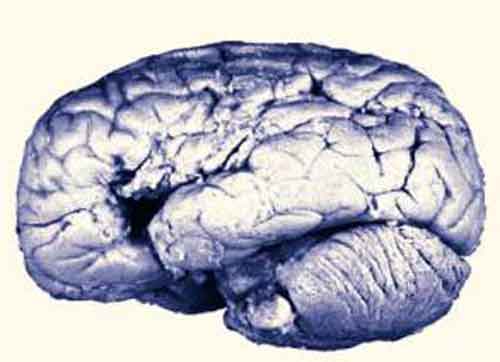

Dopo la morte, Broca eseguì un attento esame anatomico del cervello di Leborgne, premurandosi anche di conservalo presso il Musée Dupuytren di Parigi. Recenti scansioni del reperto hanno appurato che il danno subito era in realtà più ampio e profondo di quello rilevato da Broca.